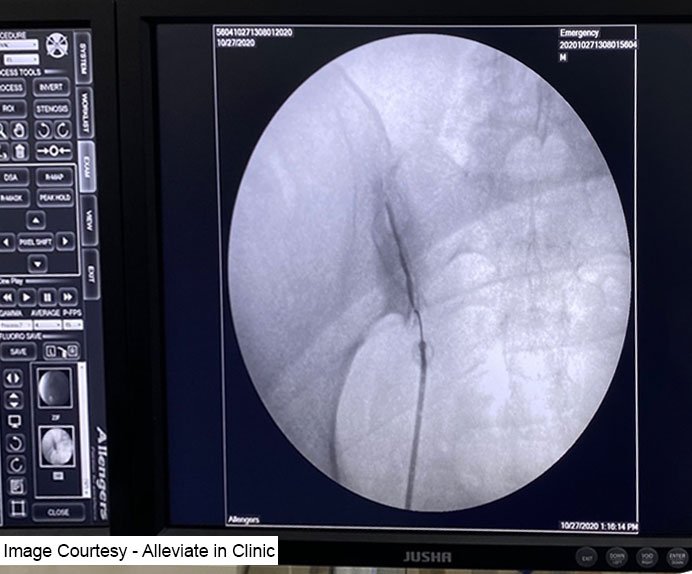

Fluoroscopy guided intrarticular Sacroiliac joint injection

Platelet Rich Plasma (PRP) therapy has emerged as a promising treatment option for sacroiliac (SI) joint pain, offering a non-surgical and minimally invasive approach to manage inflammation and promote healing. SI joint pain, characterized by discomfort and dysfunction in the pelvic region, can significantly impact mobility and quality of life. Here, we delve deeper into PRP therapy for SI joint pain, exploring its mechanisms, efficacy, and clinical applications. PRP therapy harnesses the regenerative potential of platelets, which are rich in growth factors, cytokines, and other bioactive proteins essential for tissue repair and regeneration. The procedure involves isolating and concentrating platelets from the patient’s own blood sample through a process of centrifugation. The resulting PRP solution is then injected directly into the affected SI joint under image guidance for precise delivery.Mechanisms of Action